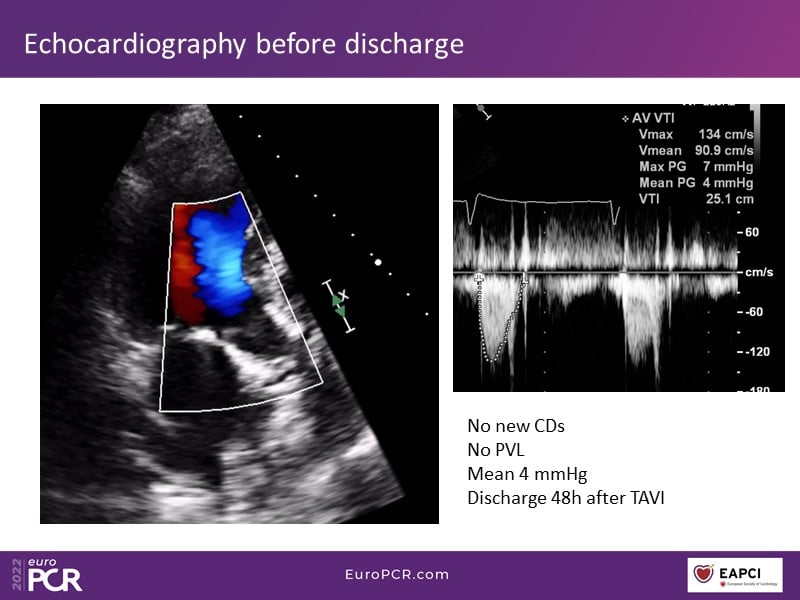

Through the presentation of real-life clinical cases, this session will allow you to discover the use of ALLEGRA for valve-in-valve TAVI, understand the management of coronary artery disease in TAVI patients, better detect when and how to protect coronary arteries during TAVI, or even learn how to perform commissural alignment with ALLEGRA.